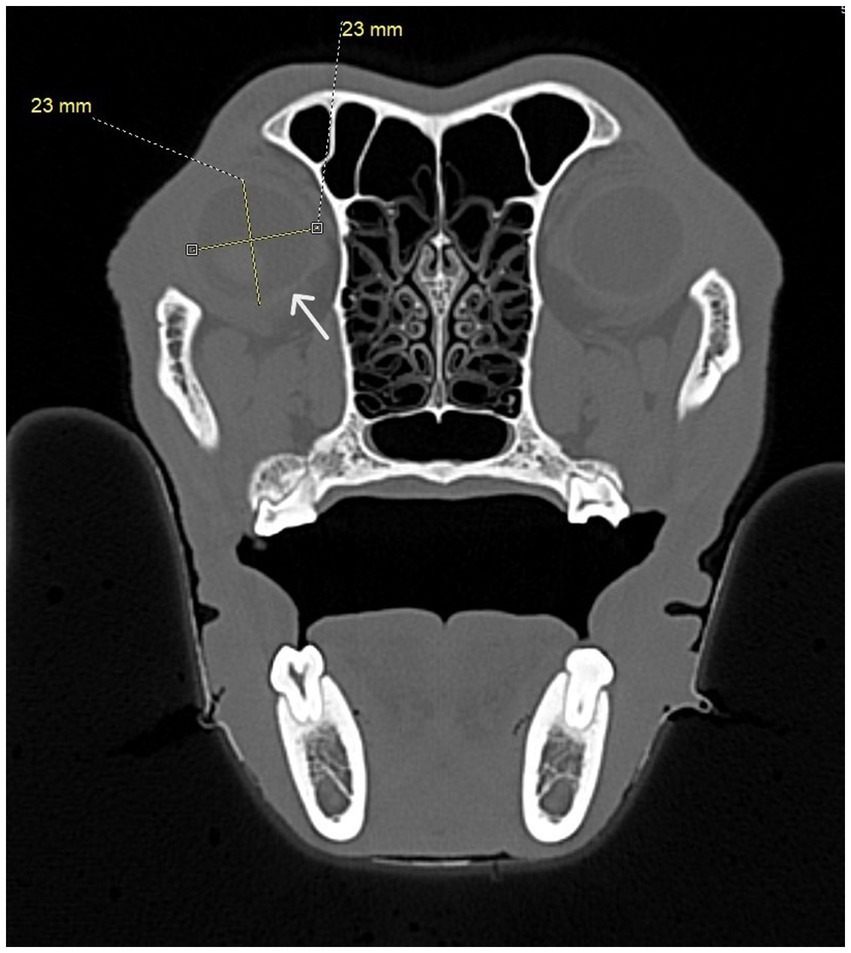

Figure 8

CT scan of a dog skull showing a cross-sectional view with a highlighted circular area 23 millimeters. An arrow points to the dog's right eye.

Figure 8. Transverse CT image showing diameter measurements taken for each eye. At least four measurements were taken at right angles to one another. The white arrow shows the border of the eye.